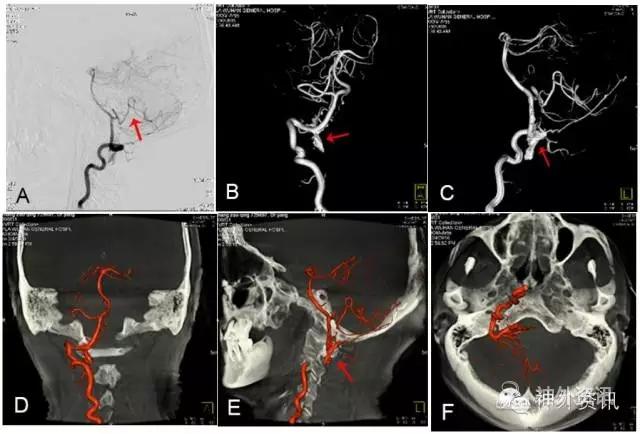

图3: 胸段硬脊膜动静脉瘘(SDAVF),↑示瘘口。A. 2D-DSA;B、C. 3D-DSA;D~F. 双容积重建冠状位、矢状位与轴位融合影像。

图3: G. 动态双容积重建冠状位融合影像。

图3: H. 动态双容积重建矢状位融合影像。

图3: I. 动态双容积重建轴位融合影像。

图3: J、K. 最大密度投影(MIP)冠状位、矢状位融合影像,可了解瘘与脊椎骨的上下左右前后的解剖关系。

图3: L. 动态旋转MIP。

图4: 右T12硬脊膜动静脉瘘(SDAVF),红色↑示瘘口,绿色↑示背侧引流静脉。A. 2D-DSA;B、C. 3D-DSA;D~F. 双容积重建冠状位、矢状位和轴位融合影像。

图4: G 动态双容积重建冠状位融合影像。

图4: H. 动态双容积重建矢状位融合影像。

图4: I. 动态双容积重建轴位融合影像。

图4: J~L. 最大密度投影(MIP)冠状位、矢状位和轴位融合影像。

图4: M. 动态旋转MIP。

图4: N~P. MRI/3D-DSA 三维融合冠状位、矢状位和轴位融合影像。